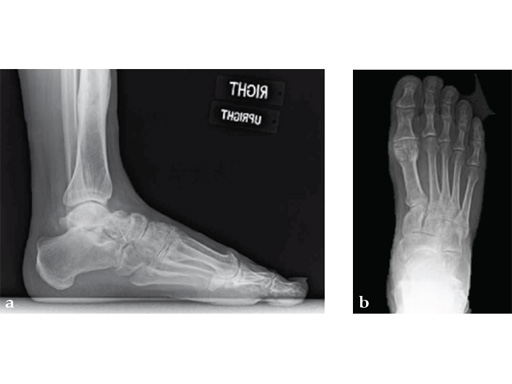

Case 8: VA -locking X-plate

A 38-year-old man fell from a 7-foot height while at work. The patient was seen at an urgent care facility and diagnosed with an ankle sprain. He was placed in a stirrup brace and instructed to bear weight as tolerated.

Case provided by Michael Castro, Scottsdale, Arizona

After 4 months the patient presented for a second opinion. His complaint was pain to the lateral column and subtalar joint. The preoperative lateral x-ray is notable for a malunited talar neck fracture with subluxation of the subtalar joint. The disproportion of the medial and lateral columns and a cavovarus position of the foot are seen on both the AP and lateral views. The degenerative changes at both the talonavicular and subtalar joints are significant.

The patient was treated with arthrodesis of the talonavicular and subtalar joints. The compression/ distraction device was used to restore the length of the medial column. The articular surface of the subtalar joint was prepared arthroscopically. The talonavicular joint was debrided then packed with a tricalcium matrix. Length was maintained using a locking X-plate. The subtalar joint was then fixed with a 6.5 mm headless compression screw.

The patient returned to work 3 months after surgery. He wears an ankle brace when on uneven surfaces. His lateral column and subtalar pain have resolved.